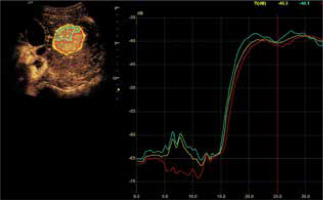

Fig. 7

Mean values of the difference in tumor enhancement and unchanged liver parenchyma over time recorded in the HCA group (blue line) and in the FNH group (red line)